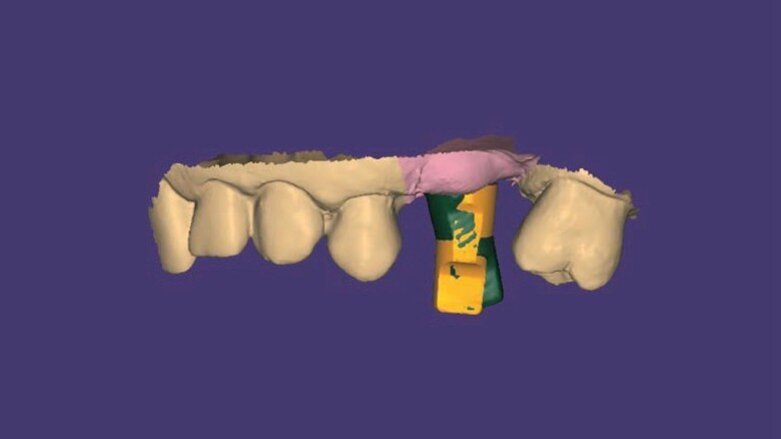

Con l’esportazione dei file STL sarà possibile realizzare una protesi avvitata disegnata con Exocad*** che dispone delle librerie protesiche REX PiezoImplant. Al momento dell’importazione del file STL nel software CAD, l’odontotecnico proporrà il matching (Fig. 8) tra il REXmarker scansionato e quello corrispondente all’interno della libreria protesica del software CAD. Conseguentemente all’allineamento “best fit” tra le due immagini (provenienti da scanner e libreria protesica) il software sostituisce l’immagine scansionata con l’immagine vettoriale, perfetta, della libreria del software. Questa immagine presenta quindi tutte le caratteristiche necessarie per la realizzazione del manufatto protesico a partire dalla modellazione della protesi sul moncone Ti Base, tenendo in considerazione anche lo spazio per l’incollaggio, alla valutazione sulla necessità di un canale dritto o inclinato per il passaggio della vite, all’analogo virtuale per la realizzazione del modello resina stampato etc. (Fig. 9).

Fig. 8 - Matching tra marker scansionato in verde e libreria protesica vettoriale in giallo.